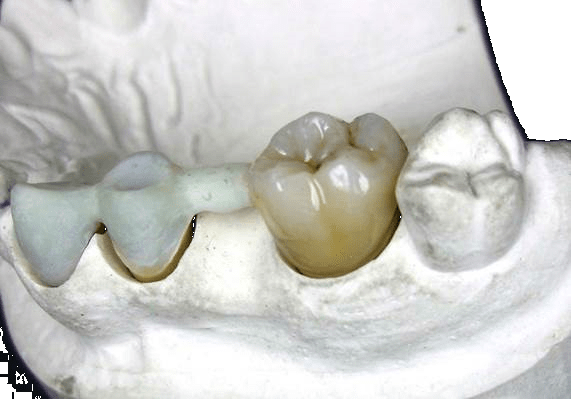

Acetal Resins

Acetal Resins provide durable, flexible, and biocompatible dental materials, ideal for aesthetic and metal-free dental restorations.

TSM Acetal Dental

Features High abrasion resistance Excellent traction and impact resistance High elastic memory Low thermal conductivity Non-allergenic and non-toxic Excellent aesthetic